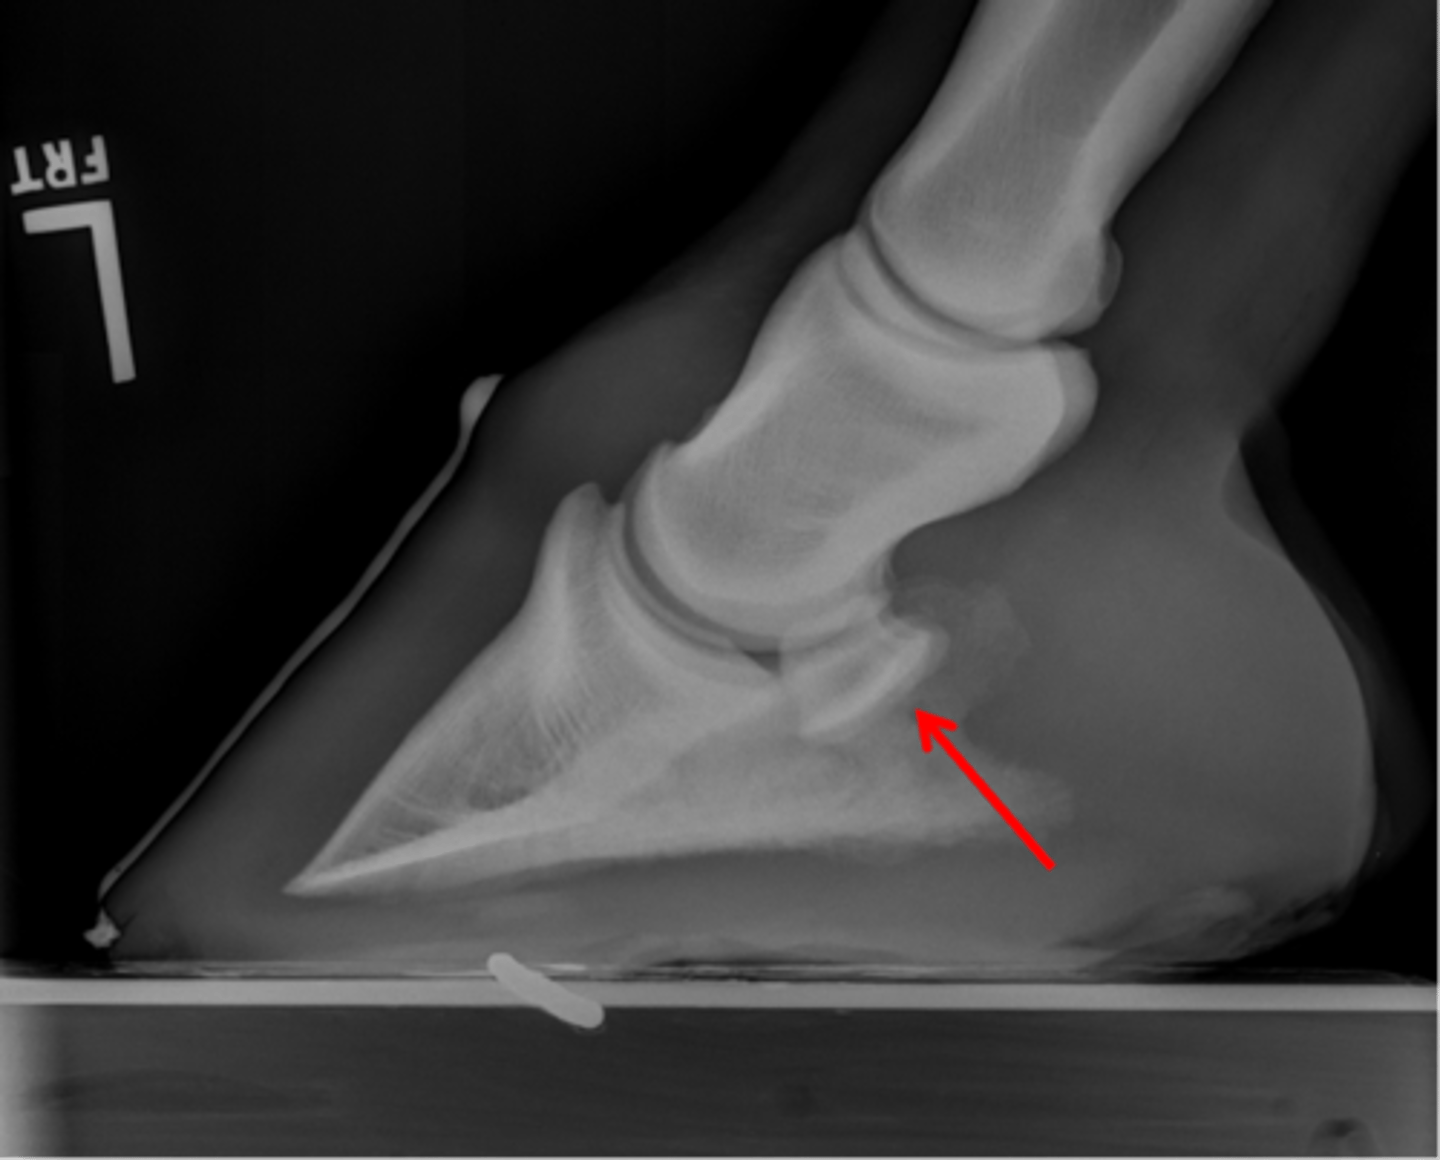

Navicular bone

Flexor cortex

Navicular bone

Proximal border of navicular bone

Distal border of navicular bone

Synovial invaginations

Navicular bone

Flexor surface

Distal border

Articular border